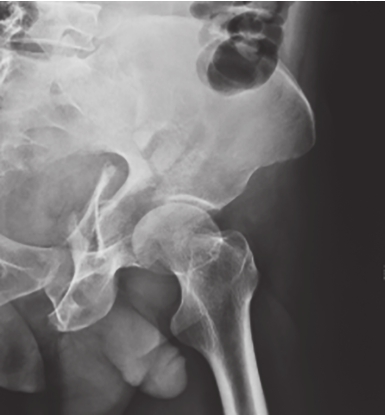

患者取仰卧位,射线倾斜45°指向头侧投射。可显示骶骨、骶孔、髂骨翼、髋臼和髂耻隆起的骨折。主要是判断半侧骨盆有无垂直移位、骶骨骨折;骨盆前环有无变宽和骨折等(图2-4)。

图2-4 骨盆出口位X线片

可见右侧骶骨骨折,提示后环损伤;L

5

横突骨折,提示骨盆骨折不稳,右半侧骨盆向上移。